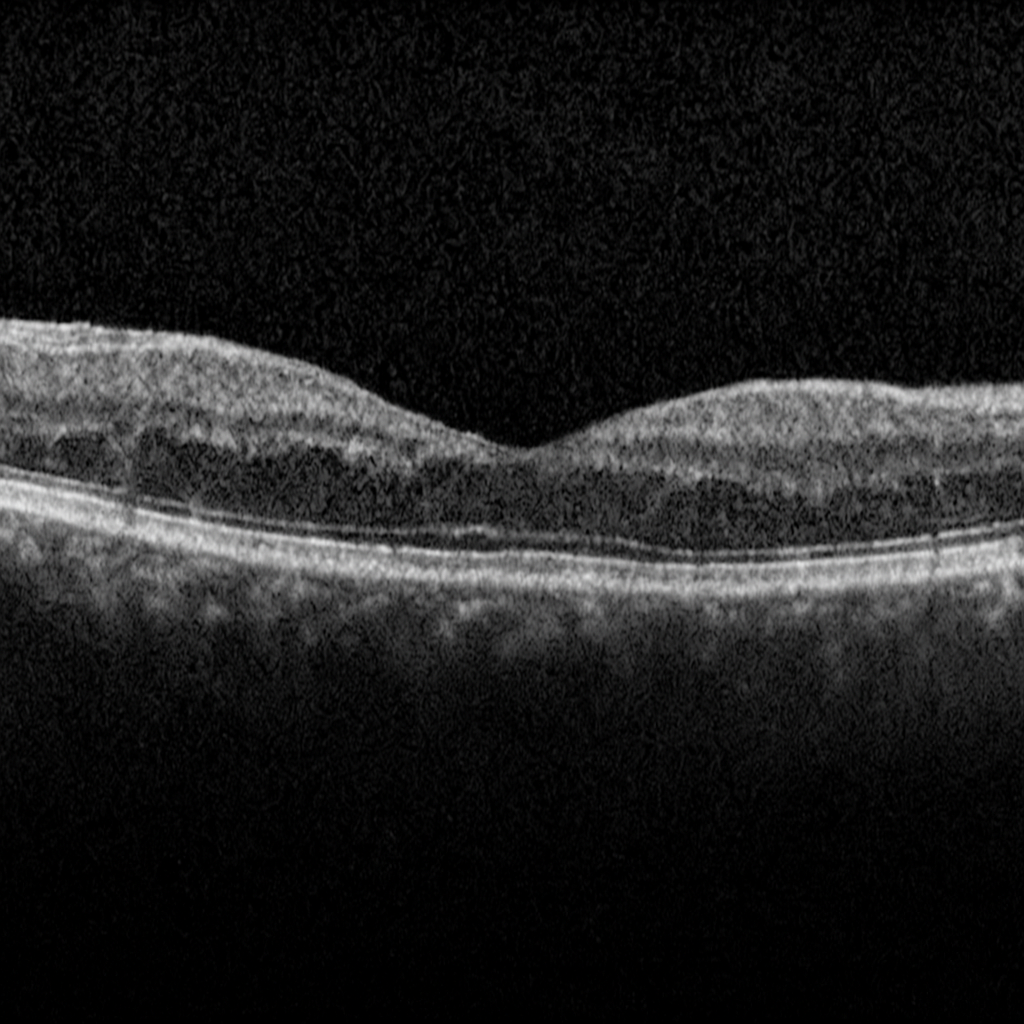

An epiretinal membrane (ERM) is a thin layer of scar-like tissue that forms on the surface of the retina, usually over the macula (the area responsible for central vision). It can cause the retina to wrinkle or contract, leading to blurred or distorted vision.

No. Many patients have mild ERM with little to no symptoms and do not need treatment. Regular monitoring with eye exams and OCT scans is often enough.